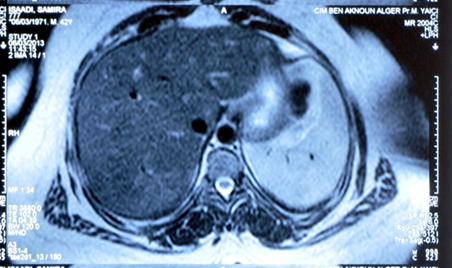

Abdominal

mri showed isointense t1-t2 hepatic micronodules suggestive of tuberculosis,

sarcoidosis, or other after-effects. One month after the operation, bilateral